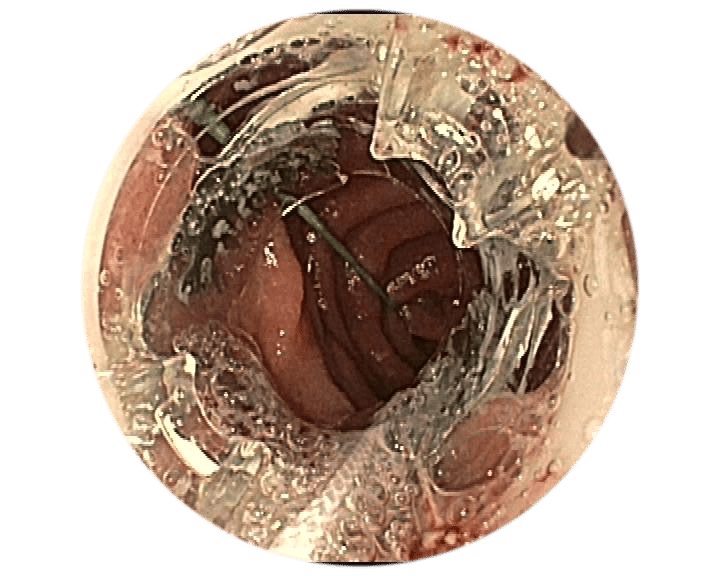

Positionsermittlung

Die korrekte Positionierung der BARS® Anchor ist entscheidend für eine erfolgreiche Behandlung.

- Mit einer gedachten Mittellinie die Anastomose in zwei Hälften teilen.

X = Austrittspunkt Endoskoparbeitskanal - Die Anchor knapp unterhalb der Mittellinie platzieren.

• = BARS® Anchor Black, • = BARS® Anchor Silver. - Der Kalibrierballon (•) definiert das Restlumen im gegenüberliegenden Halbkreis.

Beispiel 1*

Anvisieren der Applikationsstelle.

Einführen des Führungsdrahts in den äußeren BARS® Arbeitskanal und Vorlegen in der Anastomose.

Einführen der Anker in den Endoskop-Arbeitskanal und den inneren BARS® Arbeitskanal.

Überkreuztes Platzieren der Anker im vorbereiteten Zielgewebe.

Platzieren des Kalibrierballons in der Anastomose. Schrittweises Einziehen des Gewebes in die BARS® Applikationskappe, mit abwechselnden Zugbewegungen.

Sicherstellen, dass das Gewebe symmetrisch in der Kappe positioniert ist. Platzieren des BARS® Clips durch Drehen des Handrads.

Zurückziehen der Instrumente und Inspektion der Clip-Applikationsstelle.

1Quelle: Dr. med. M. Kandler, Städtisches Klinikum Dresden, Deutschland